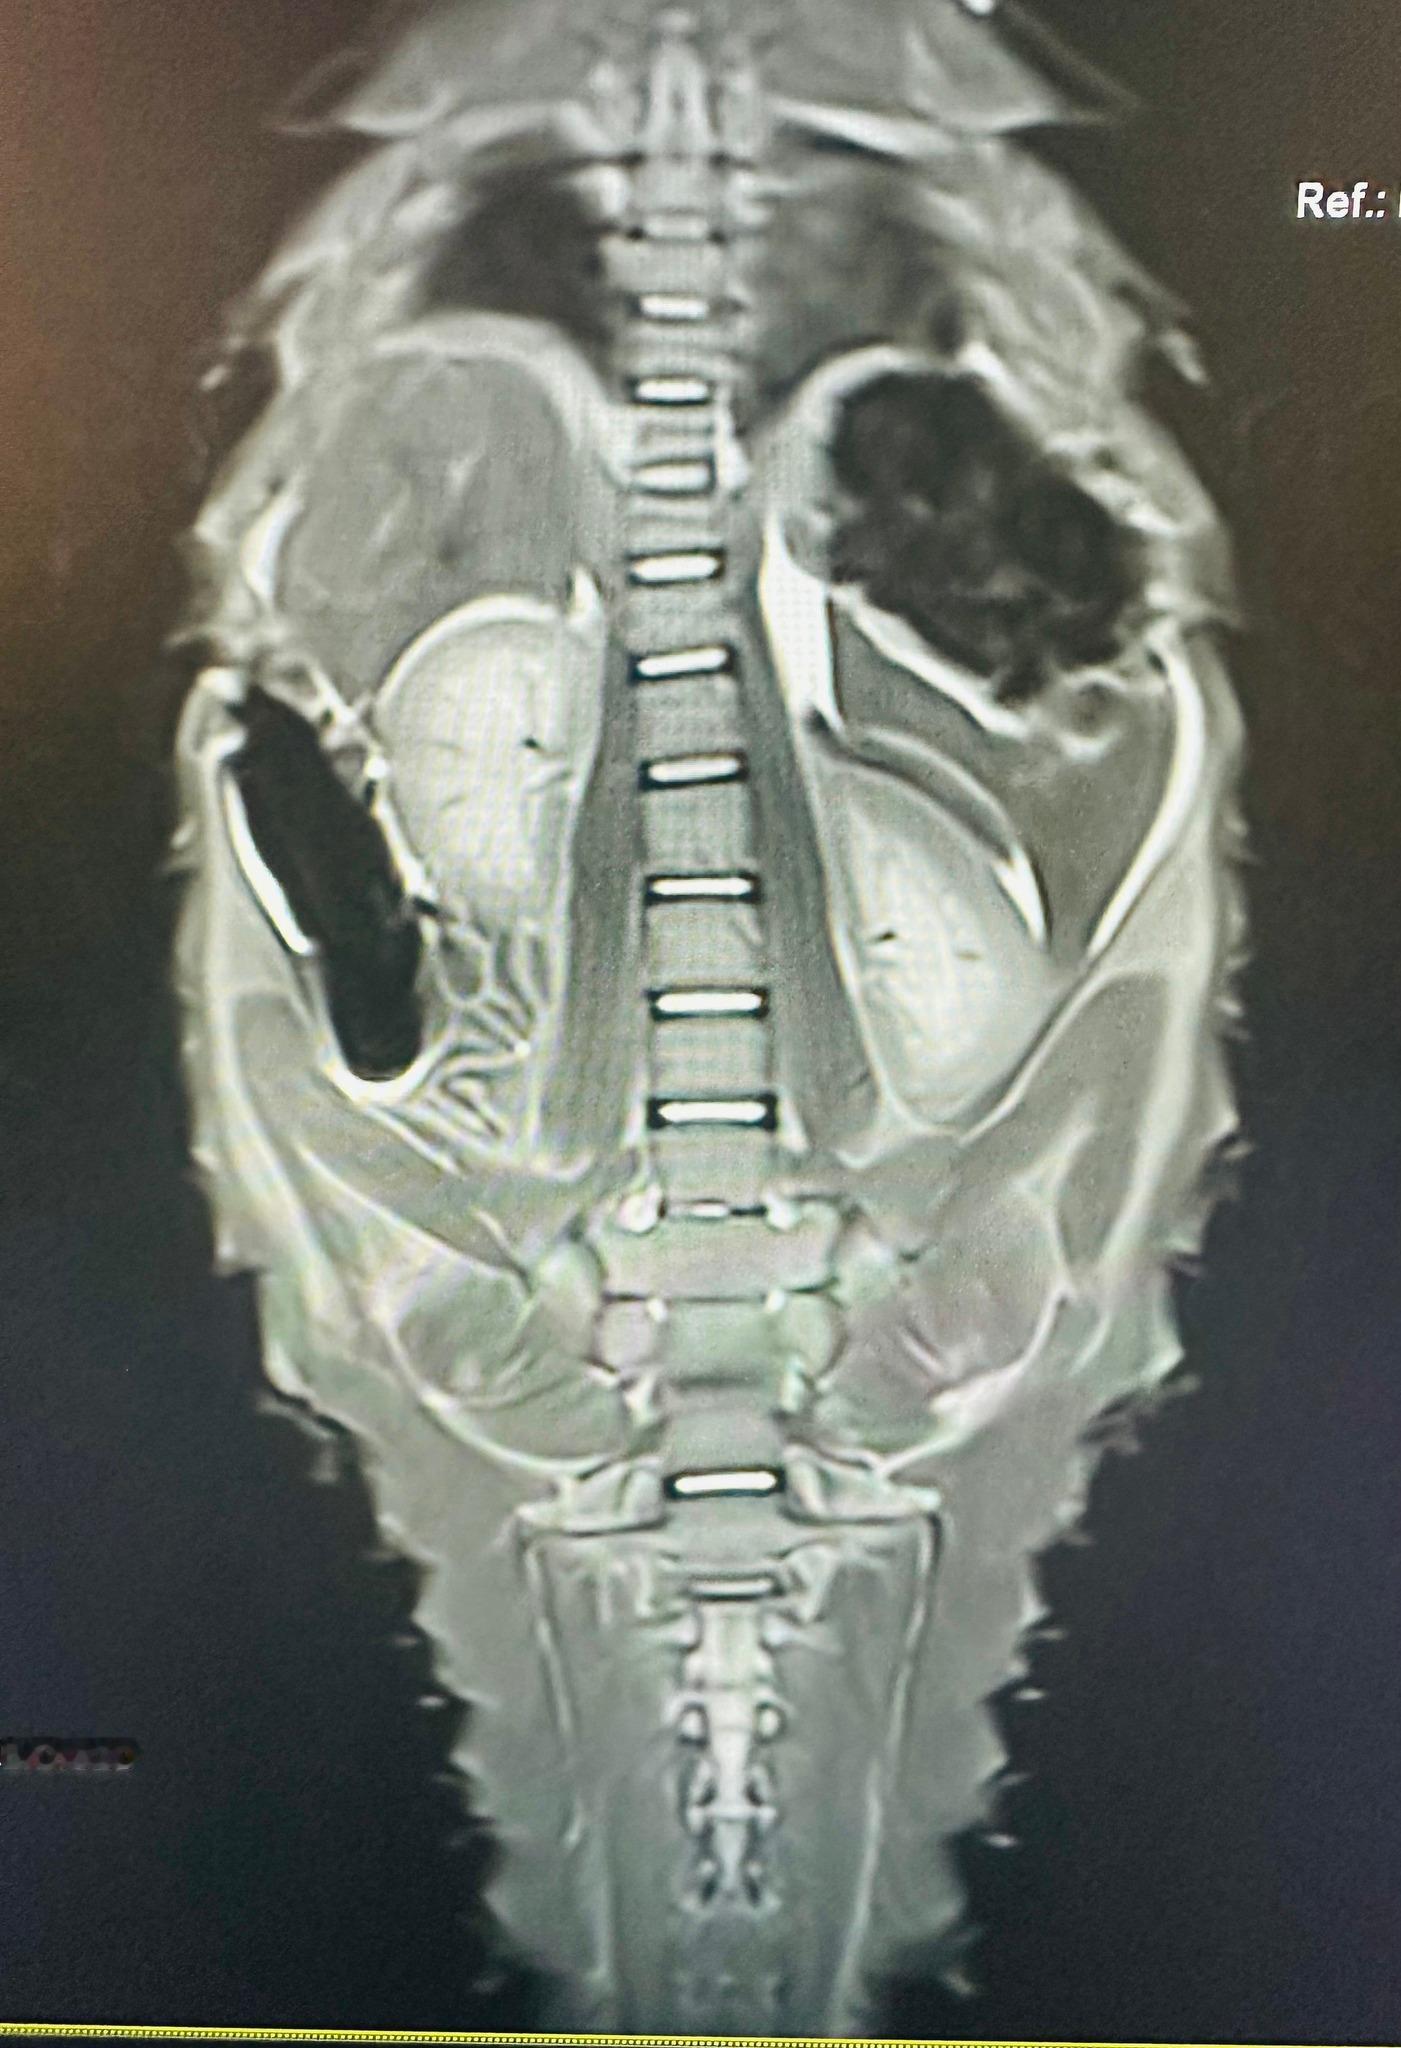

这只叫做Heritage的雌性穿山甲,在南非被从非法交易中解救出来的时候,有着严重的脊柱感染情况。当时大家都不太乐观,因为首次在救助的穿山甲身上发现这种病例。但是经过野生救护人员的悉心救助和护理,60天的高强度治疗后,再次做核磁共振检查时候发现她已经完全康复啦!!感谢所有付出努力的人们~也感谢高度配合的Heritage自己~努力获得了新生图1看到那个小脑袋,原谅我真的笑了半天【脸书:Umoya Khulula Wildlife Centre】